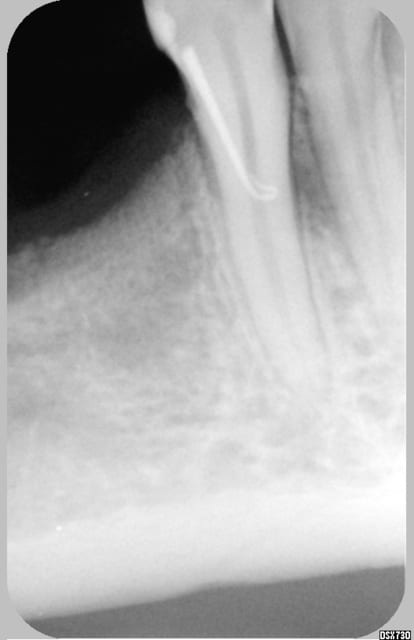

Et la soluce est.......poche en linguale...la preuve sur la RX. Comme quoi, même en cherchant une fois, ça suffit pas toujours. Dans le cas présent, la sonde m'a induit en erreur...mais pas le cône de gutta !! (encore une raison d'adorer ce matériau ! ;-) )

Pour le traitement : pour l'instant, abstention thérapeutique car il y a d'autres soucis (cf 2° radio jointe, qui n'est qu'un exemple). Et en plus je sais pas trop quoi lui proposer pour une poche comme ça.

La patiente à une hygiène très correcte, d'autres problèmes paro localisés et c'est une dent support de crochet...

Donc soit purement parodontal sans que la dent y soit pour quelque chose, soit fêlure longitudino-transversale qui crée une sorte de fistule desmodontale en regard.

Même si la dent n'est pas sensible aux variations thermiques, je penche pour cette deuxième possibilité (d'où abstention thérapeutique pour l'instant).